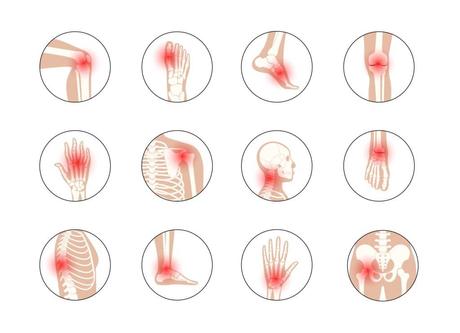

Les rhumatismes regroupent un ensemble de maladies affectant les articulations et les structures environnantes comme les tendons, les ligaments et les muscles. Ces pathologies sont souvent associées à une inflammation, entraînant une douleur significative. Plusieurs études ont suggéré que le CBD pourrait être utile pour traiter ces douleurs :

L’arthrose est une maladie articulaire fréquente, en particulier chez les personnes âgées. Elle se manifeste par une dégradation progressive du cartilage, provoquant des douleurs et une diminution de la mobilité. Plusieurs recherches ont également examiné les effets du CBD sur l’arthrose :

Les rhumatismes englobent une variété de conditions impliquant une inflammation et une douleur dans les articulations ou les muscles. Le cannabidiol (CBD), un composé non psychoactif dérivé du cannabis, a suscité un intérêt croissant pour le traitement des rhumatismes en raison de ses propriétés anti-inflammatoires et analgésiques.